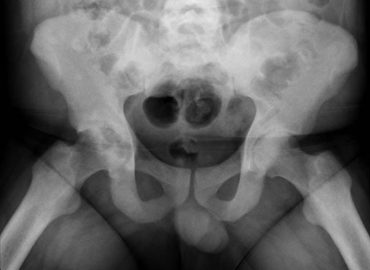

Mujer de 28 años con coxalgia derecha progresiva de un año de evolución.